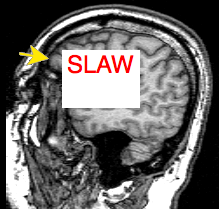

If you want your head to know more about your head, you could consult Brain Explorer, a Lundbeck Institute site that offers you a brain atlas, with pictures and explanations. Or go to the Harvard Whole Brain Atlas, where you’ll find nifto cross sections of the think stuff done by PET scans and you can locate your amygdala from above, the side and the front.